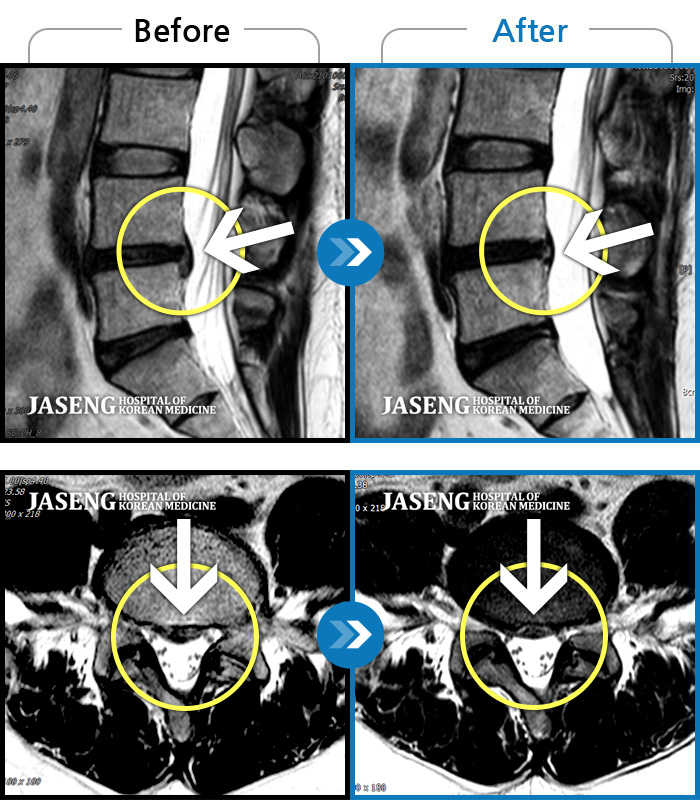

Before

After

허리 통증과 함께 발끝 저림이 1년 이상 되었으며 최근 1-2개월 사이에 증상이 급격히 심해져 우측 다리 앞 뒤가 당기고 힘이 빠져 본원에 내원함

2023.11.20 ~ 2024.08.12